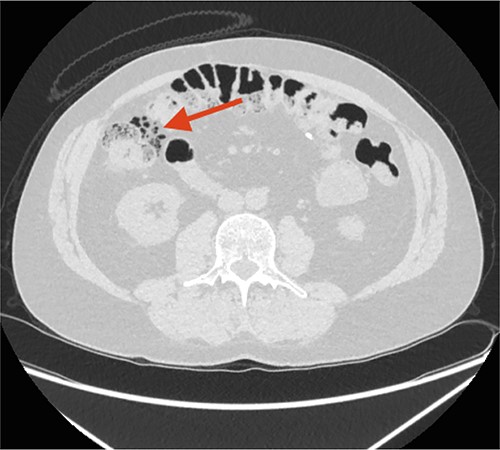

Two days later, the patient returned with intensified pain in the left flank, and a CT scan showed a calculi in the left ureter and progression in the free air located along the ascending colon (Fig. 2). The patient had no abdominal physical signs indicative of peritonitis, no fever and normal blood test.

CT scan performed 2 days after the first admission to the Emergency Department (ED). The arrow points at remaining FIA along the ascending colon/right flexure.